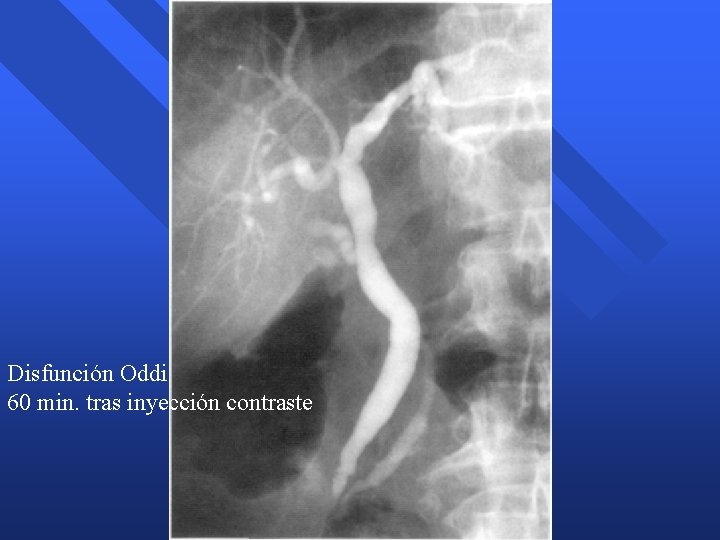

Disfunción Esfínter Oddi n Definición – Anomalías motoras del esfínter de Oddi n Síntomas – Dolor abdominal recurrente n Alteraciones analíticas – Elevación enzimas hepáticas / bilirrubina – Elevación amilasa n Alteraciones radiológicas – Dilatación conducto biliar / retraso drenaje – Cambios calibre Wirsung / retraso drenaje

Disfunción Esfínter Oddi n Tipos – Biliar – Pancreático n Diagnóstico – Manometría del Esfínter de Oddi » Aumento presión basal (> 40 mm. Hg) » Taquioddia (aumento frecuencia / amplitud) » Efecto paradójico de la CCK (contrae) n Tratamiento – Esfinterotomía

Disfunción Oddi 60 min. tras inyección contraste